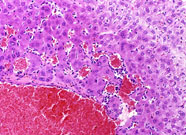

A hemangioma has destroyed the normal hepatic parenchyma. A thrombus is present at the top of the hemangioma; high magnification shows dilated vascular channels lined by flattened endothelial cells. There is minimal atrophy of hepatic cords.